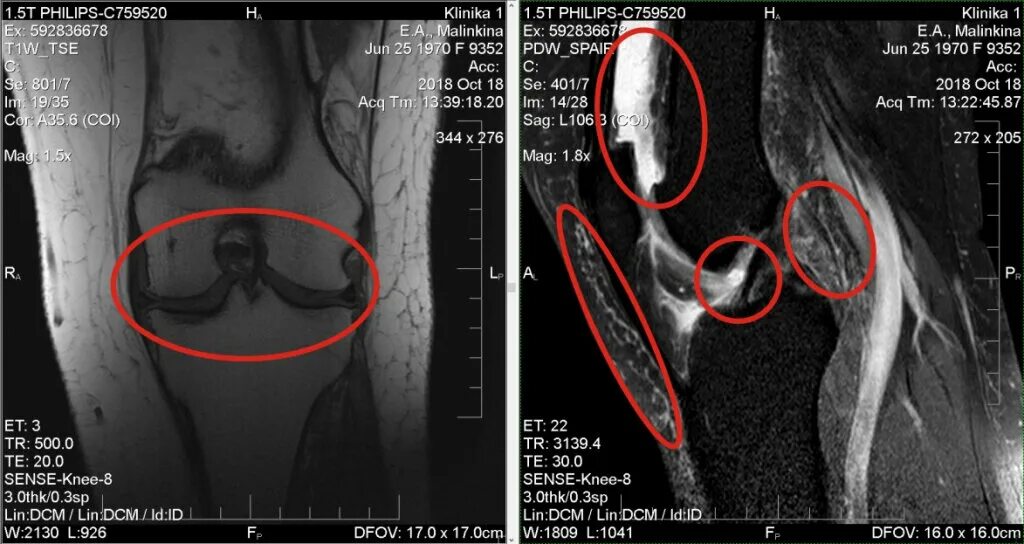

Мрт при боли в суставах